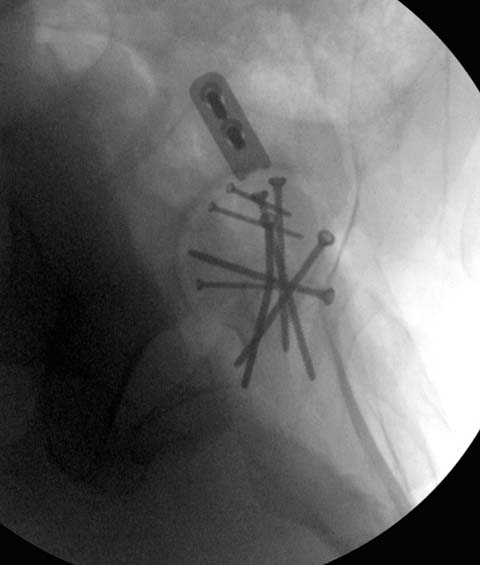

Здесь выбрана правильная тактика и операция сделано на хорошо. Надеюсь, промах с фиксацией не создаст проблему. Можно было добавить в задную стенку spring plate и винты до медиального кортекса в фиксации вертела.

Здесь клинические примеры: Первый случай передний доступ, второй с ICP monitor Flipp Trochanteris

и с переломом заднего края.